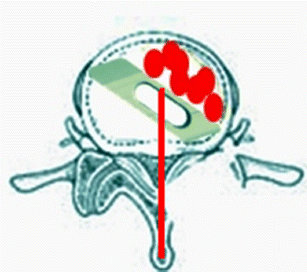

Fig. 2